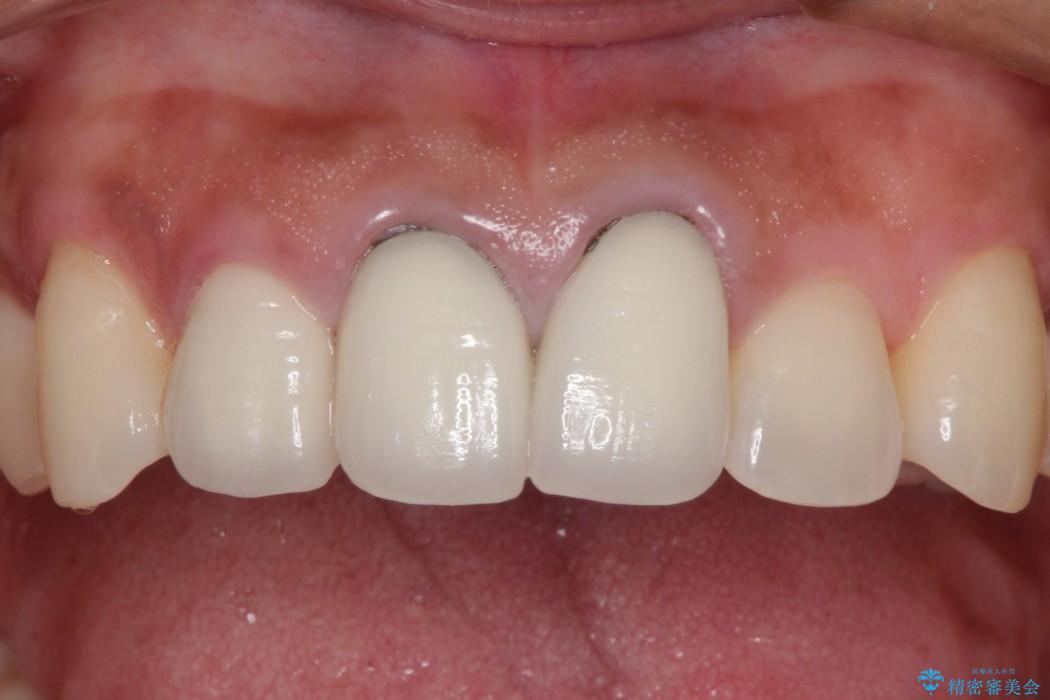

前歯の歯ぐきとの境いめが黒く変色していることを主訴にご来院されました。

以前に他院で金属の土台とセラミックの被せものによる治療をされていました。

金属を用いた治療では、時間が経過していくと口腔内に金属イオンが徐々に溶出し、歯や歯肉が黒くなることがあります。